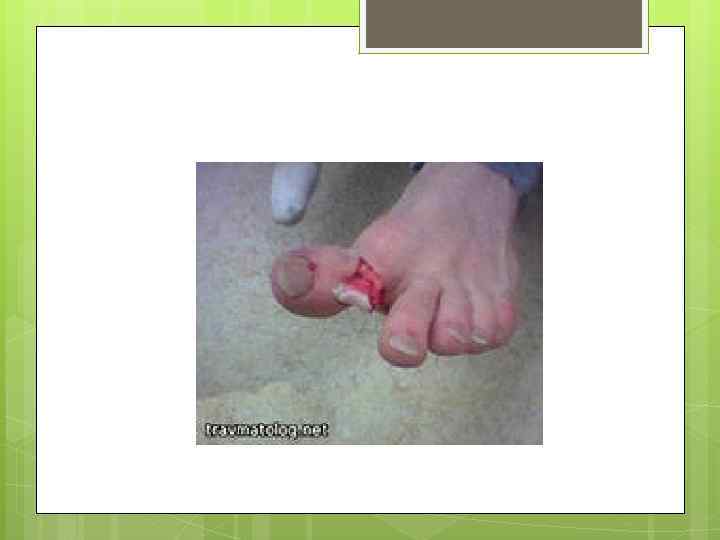

При открытых переломах В ране могут быть видны отломки костей. Переломы костей конечностей сопровождаются их укорочением и искривлением в месте перелома. Повреждение ребер может утруднять дыхание, при ощупывании в месте перелома слышен хруст (крепитация) отломков ребра. Переломы костей таза и позвоночника часто сопровождаются расстройствами мочеиспускания и нарушением движений в нижних конечностях. При переломах костей черепа нередко бывает кровотечение из ушей.

При открытых переломах В ране могут быть видны отломки костей. Переломы костей конечностей сопровождаются их укорочением и искривлением в месте перелома. Повреждение ребер может утруднять дыхание, при ощупывании в месте перелома слышен хруст (крепитация) отломков ребра. Переломы костей таза и позвоночника часто сопровождаются расстройствами мочеиспускания и нарушением движений в нижних конечностях. При переломах костей черепа нередко бывает кровотечение из ушей.